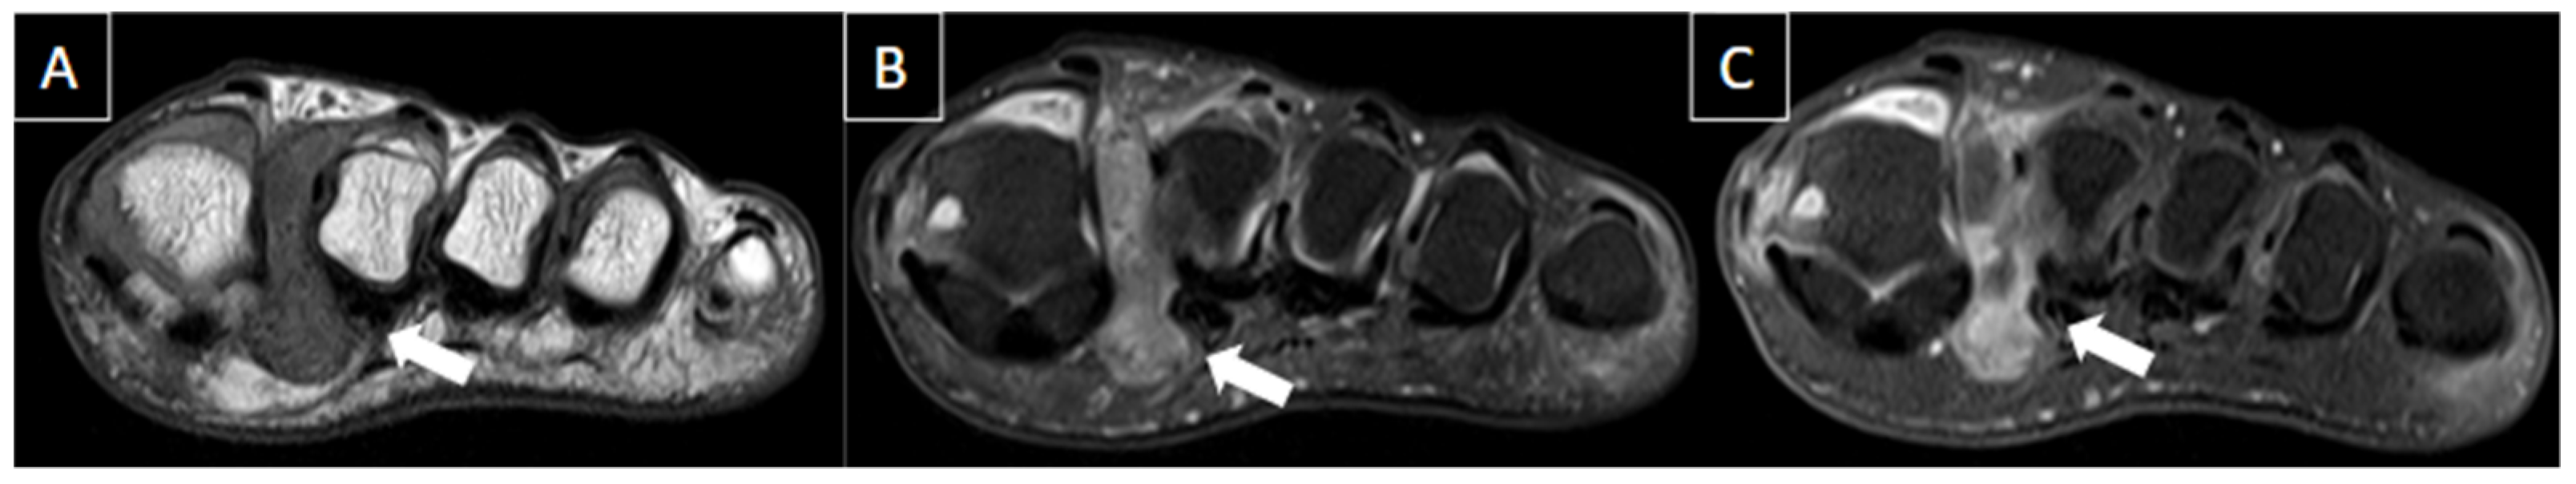

| Perivascular edema and enhancement Muscle edema Intraluminal signal change Venous enlargement Presence of collateral veins Venous filling defects (post-gadolinium injection) | Local tenderness Loss of compressibility Venous enlargement Intraluminal content Perivascular edema | Local tenderness Loss of flow Filling defects |

| Ganglion/synovial cysts | Mass effect on adjacent structures (frequently related to trauma history). | Well-defined uni or multilocular fluid-filled anechoic masses with posterior acoustic enhancement. | Mass with water equivalent signal (uniformly hyperintense on T2), and the walls can show post-gadolinium enhancement. |